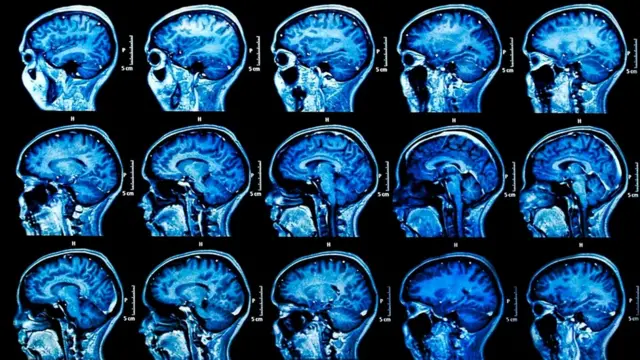

Тот самый вирус, который вызывает простуду на губах, судя по всему, наносит и долговременный урон головному мозгу человека. Это открытие может предложить новые способы лечения старческого слабоумия, пишет Рут Ицхаки в своей статье на сайте Conversation, которую мы перепечатываем.

Более 30 млн человек по всему миру страдают болезнью Альцгеймера, наиболее распространенной формой деменции. К сожалению, это заболевание не лечится, есть только лекарства, которые способны облегчить его симптомы.